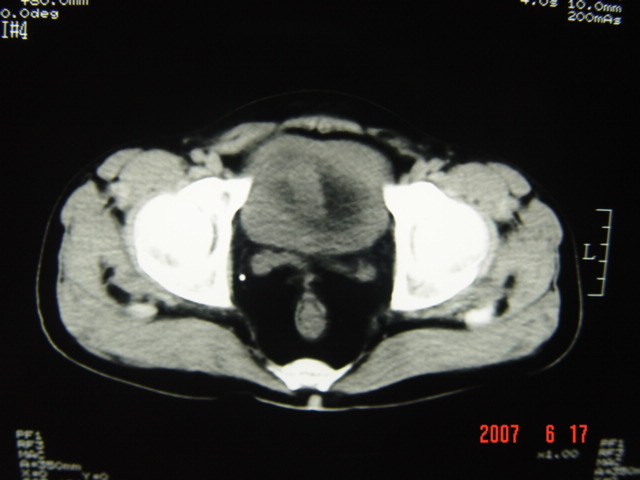

[br][br]以下是引用lkc8963在2007-6-17 13:32:00的发言:[br]完全支持邓主任意见:降/乙交界部占位性病变伴不全梗阻.做个增强或者be可能更好.